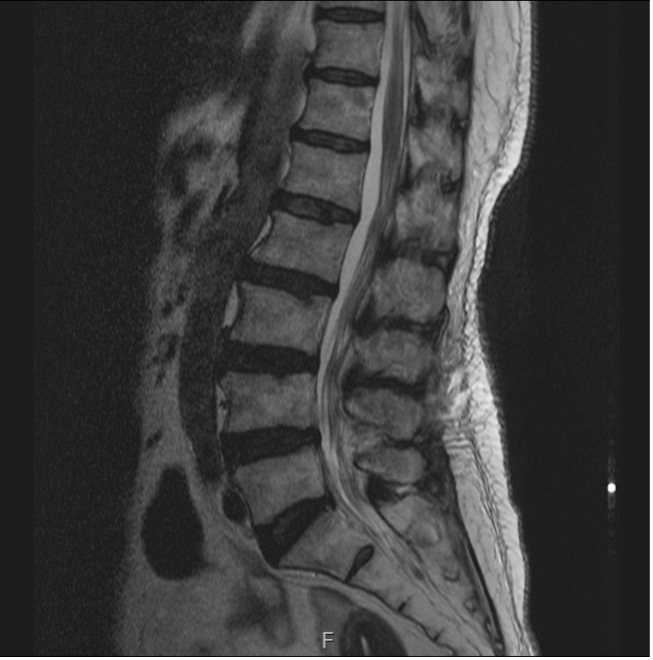

수술 전

수술 후